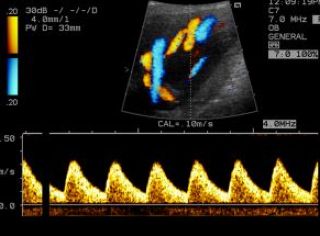

Beurteilt wird auch der Ductus venosus, eine fetale Gefäßverbindung zwischen der Nabelschnurvene und der unteren Hohlvene. Seine Blutflussmessung erlaubt die Abschätzung der fetalen Herzfunktion. Auffällige Flussmuster sind häufiger mit Chromosomenstörungen und Herzfehlern assoziiert, können zu diesem Zeitpunkt aber auch bei 3-4% aller gesunden Feten vorkommen.

Fet ohne darstellbares Nasenbein (Pfeil) und mit verdickter NT Normales Blutflussmuster im Ductus venosus

Mittels dieser Untersuchung werden Blutflußmuster in mütterlichen und kindlichen Blutgefäßen mit einer speziellen Ultraschalltechnik dargestellt.

Durch die Beurteilung der Blutflussmuster in den Gebärmutterarterien kann ein erhöhtes Risiko bezüglich einer Mangelversorgung des Feten (Plazentainsuffizienz) oder einer Präeklampsie (schwangerschaftsbedingter Bluthochdruck und Eiweißausscheidung im Urin) bereits zwischen der 20. -24. Schwangerschaftswoche erkannt werden. In diesem Fall kann eine intensivierte Überwachung der Schwangerschaft notwendig sein.

Gebärmutterarterie

Nabelschnurarterie

Durch die Messung der kindlichen Blutflüsse in Arterien und Venen kann die Versorgung des Feten beurteilt werden. Insbesondere bei einer kindlichen Mangelentwicklung kann durch diese Untersuchungsmethode eine effektive Überwachung des Kindes gewährleistet werden. Auffällige Blutflussmuster können Hinweise auf eine kindliche Gefährdung sein, die eine vorzeitige Entbindung nötig machen.